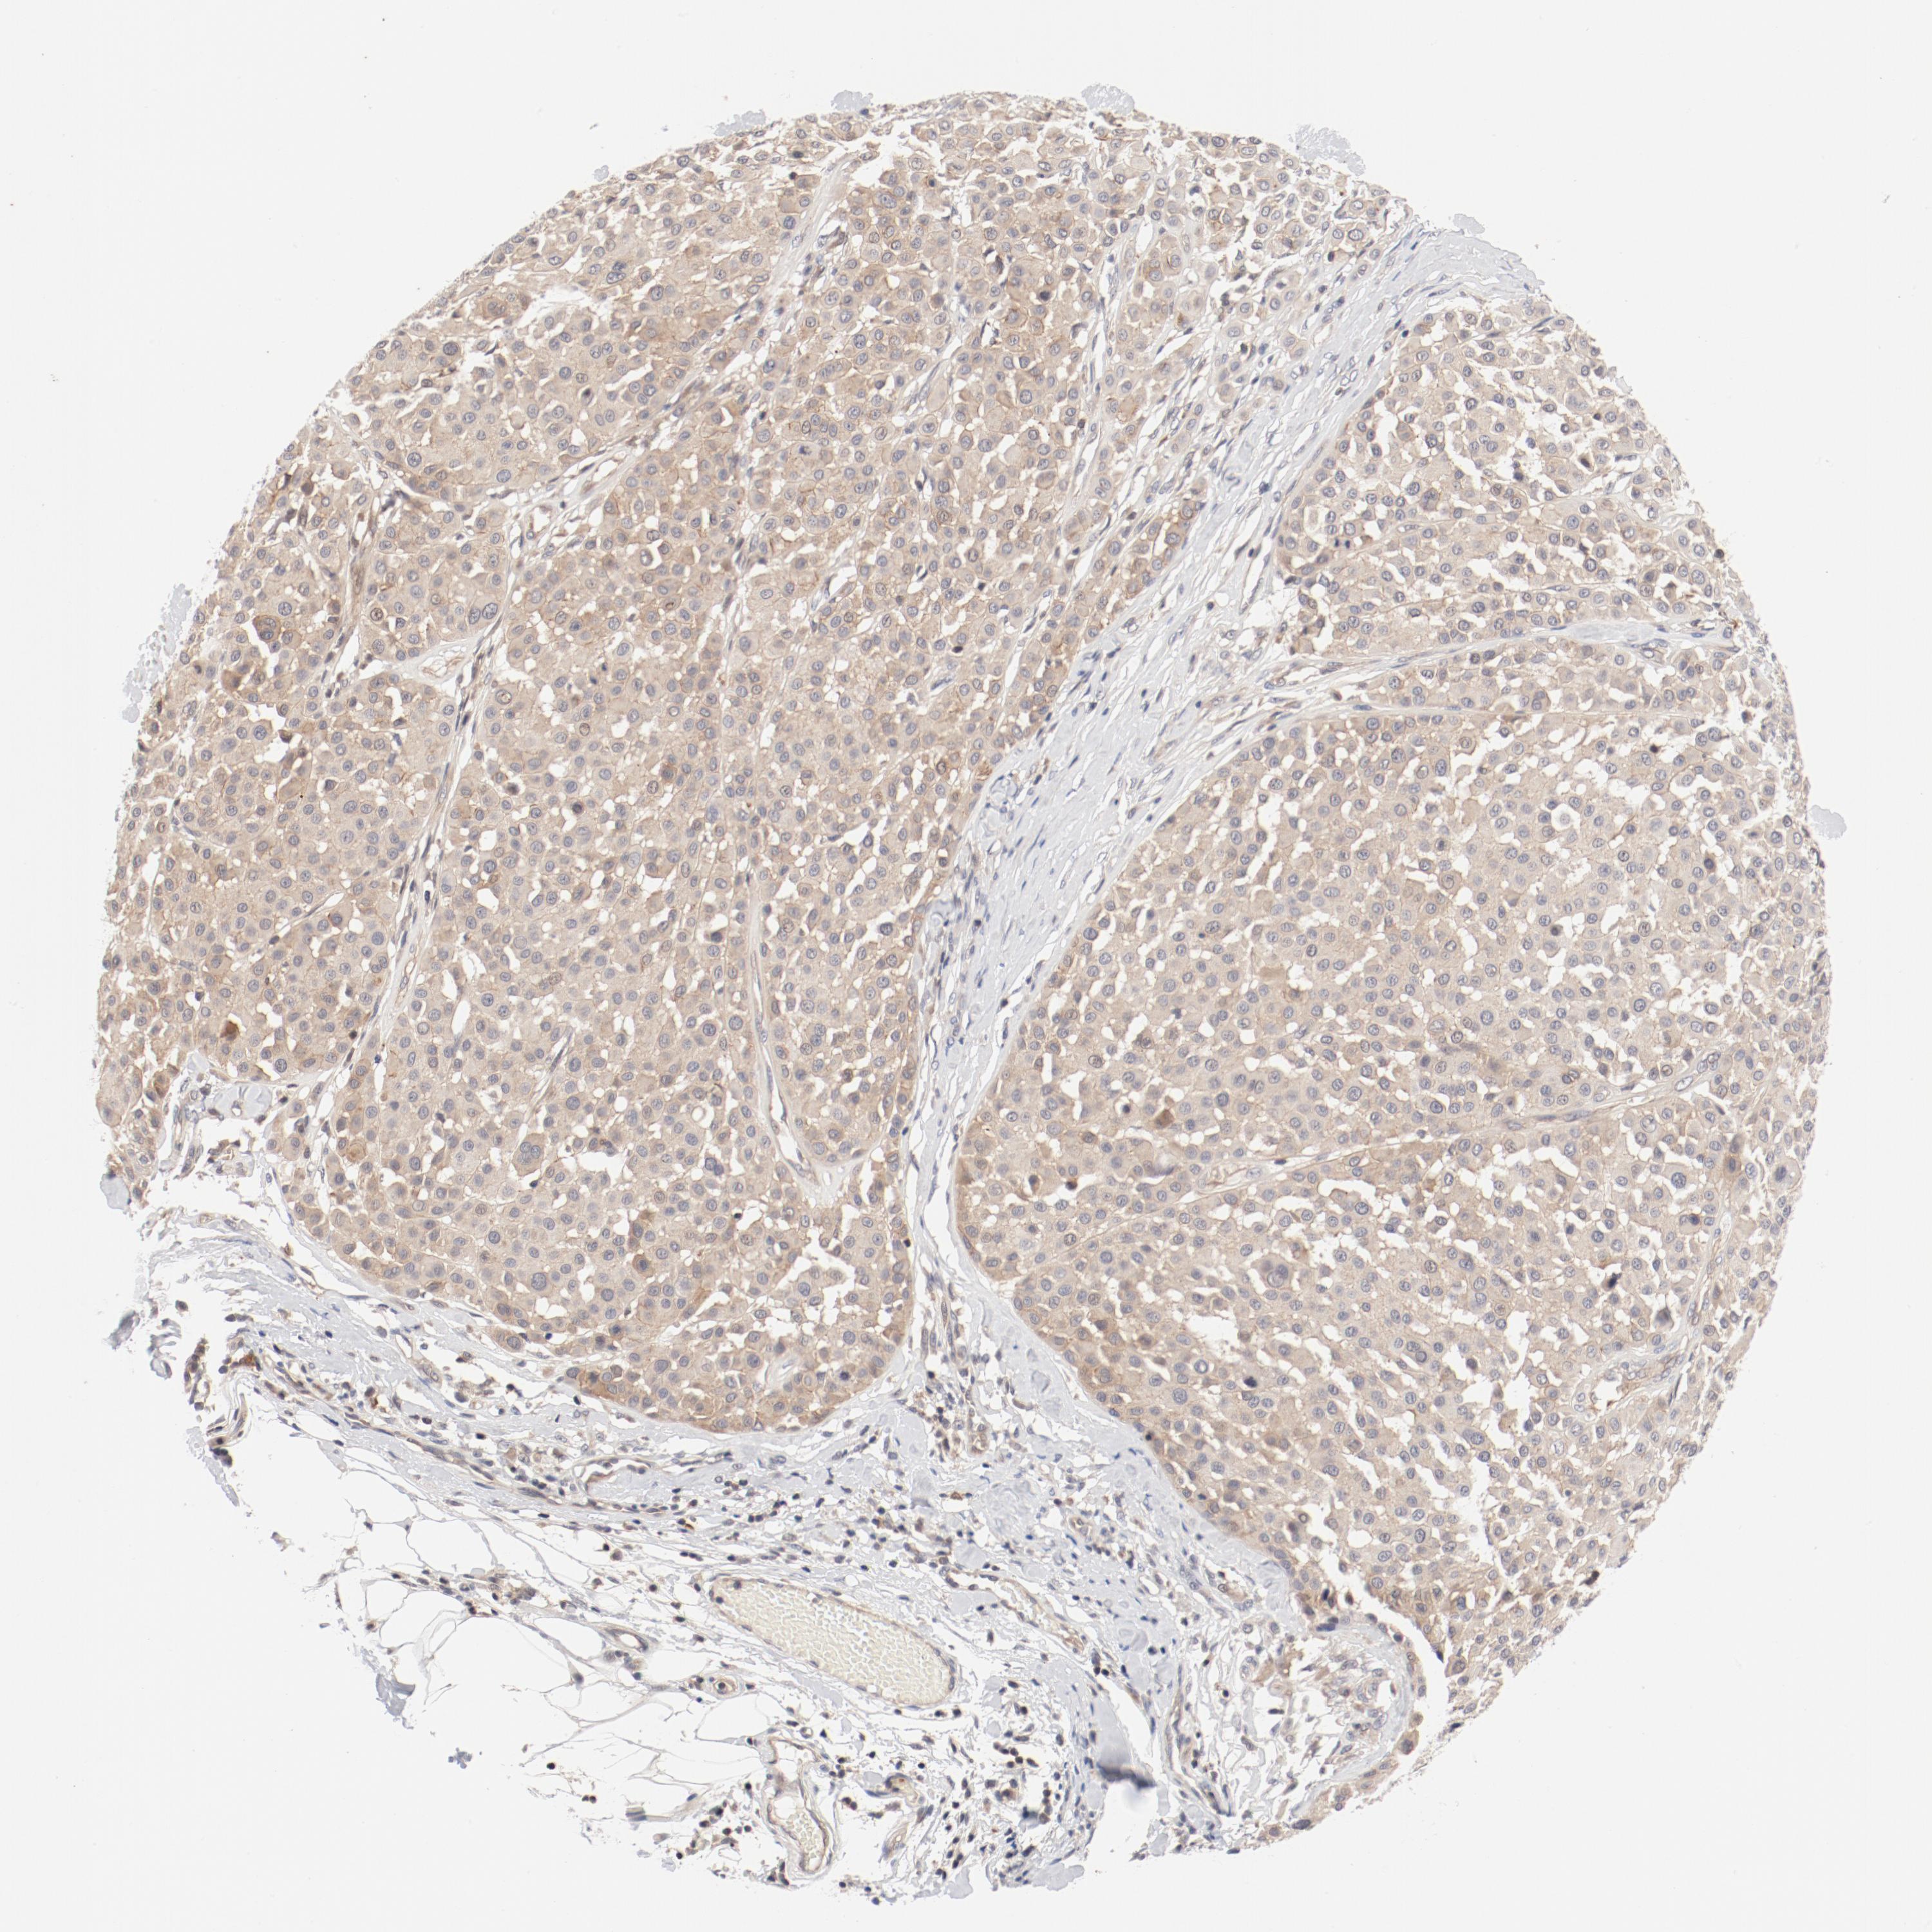

MELANOMA - Protein expressioni

A mouse-over function shows sample information and annotation data. Click on an image to view it in a full screen mode. Samples can be filtered based on level of antibody staining by selecting one or several of the following categories: high, medium, low and not detected. The assay and annotation is described here.

Note that samples used for immunohistochemistry by the Human Protein Atlas do not correspond to samples in the TCGA dataset.

Antibody stainingi

Antibody staining in the annotated cell types in the current human tissue is reported as not detected, low, medium, or high, based on conventional immunohistochemistry profiling in selected tissues. This score is based on the combination of the staining intensity and fraction of stained cells.

Each image is clickable and will lead to virtual microscopy that enables deeper exploration of all samples and also displays staining intensity scores, fraction scores and subcellular localization as well as patient and tissue information for each sample.

Antibody HPA003866

Staining

High

Medium

Low

Not detected

Intensity

Strong

Moderate

Weak

Negative

Quantity

>75%

75%-25%

<25%

None

Location

Nuclear

Cytoplasmic/membranous

Cytoplasmic/membranous,nuclear

Malignant melanoma, NOS

Malignant melanoma, Metastatic site